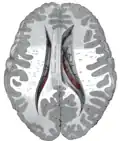

Coronal section through anterior cornua of lateral ventricles.